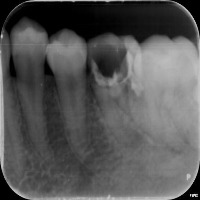

Dental Health Monitoring: This computer vision model can be used by dental professionals and healthcare providers to monitor patients' dental health by evaluating teeth x-rays and identifying specific classes to detect decay, infections, or tooth misalignment.

Dental Education and Training: Dental students and professionals can leverage this model as a learning tool to study and understand different vqc classes, such as P3, P4, and P5, and their implications in various dental conditions and their corresponding required treatments.

Customized Orthodontic Treatment Planning: The model can analyze x-rays to identify individual tooth structure, allowing orthodontists to create customized and more precise treatment plans for improving dental alignment and addressing various occlusion issues.